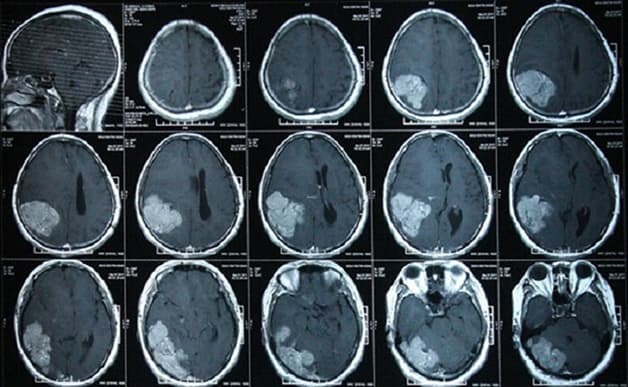

Hình ảnh chụp CT sọ não